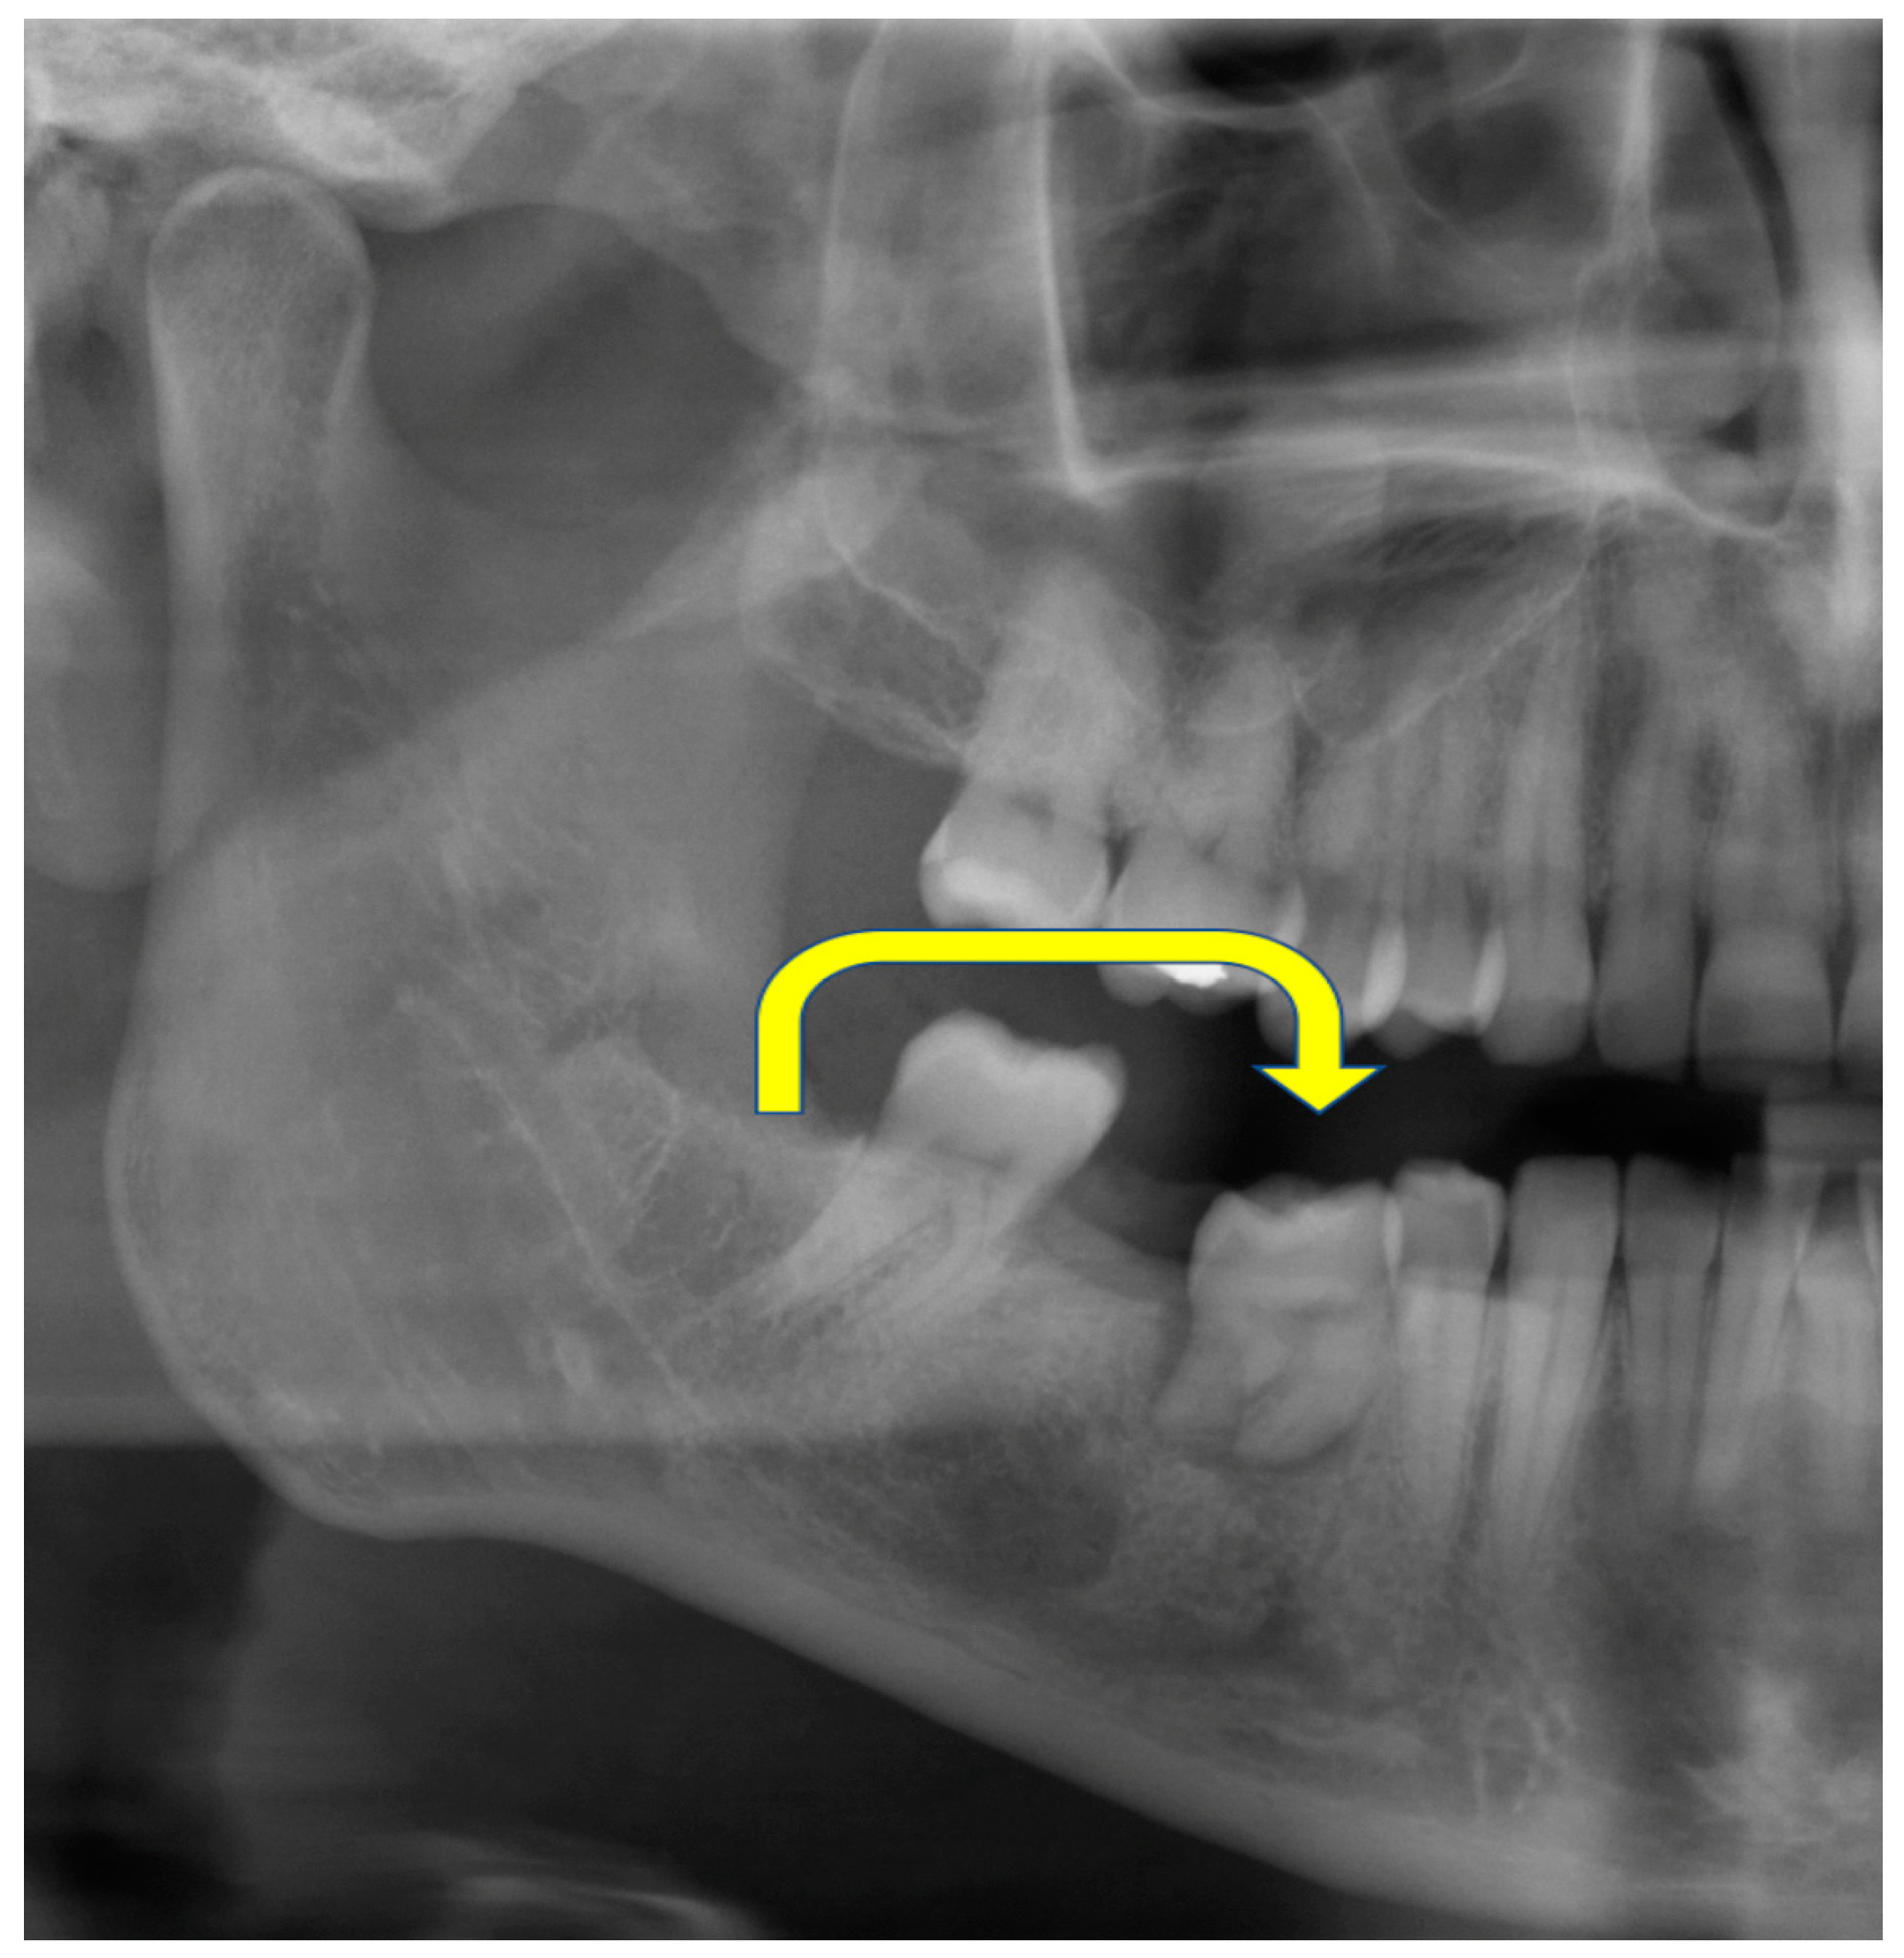

2. Report